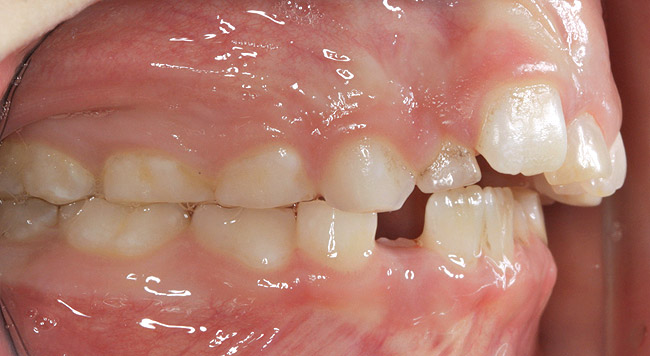

(3.) Three-year-old with a history of snoring, bruxing, and thumbsucking. Her father and brother were both diagnosed with OSA.

Figure 3

(4.) Patient presents bilateral crossbite and significant attrition. Father assists in retraction.

Figure 4